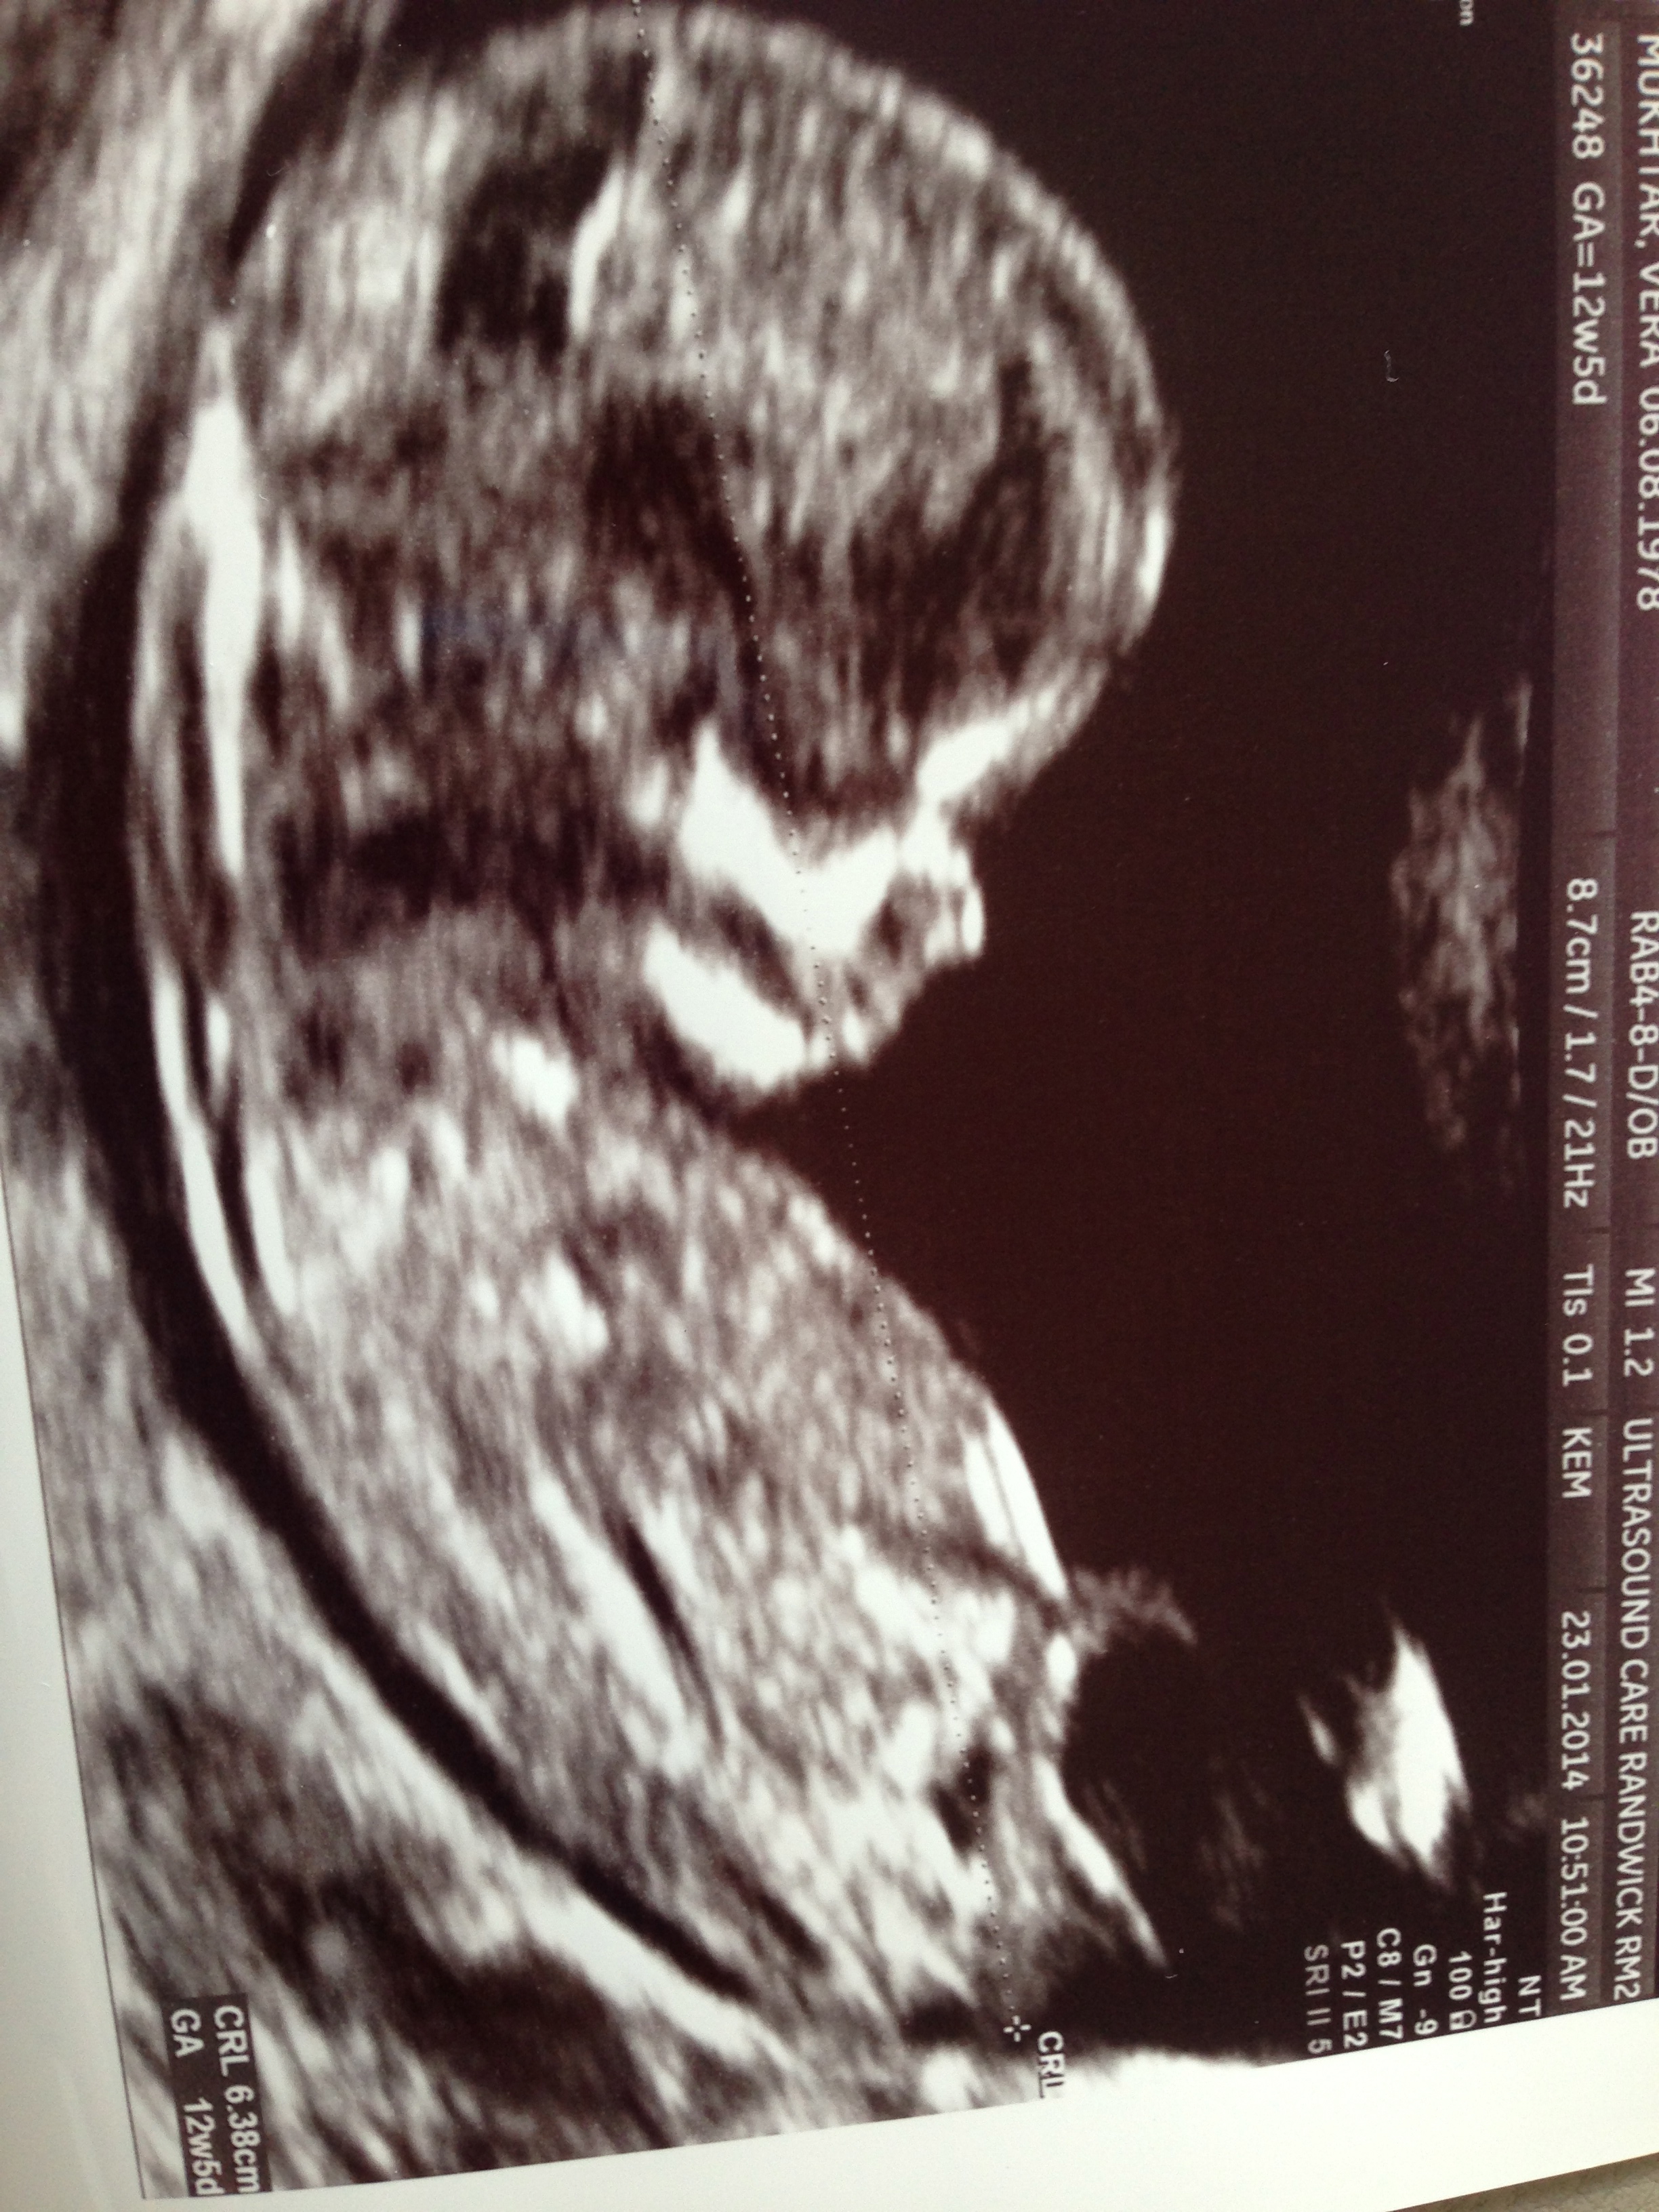

Thank you Aidansmum, much appreciated! Attachment 16730ill attach another one.

I think girl xx

Girl guess from me!